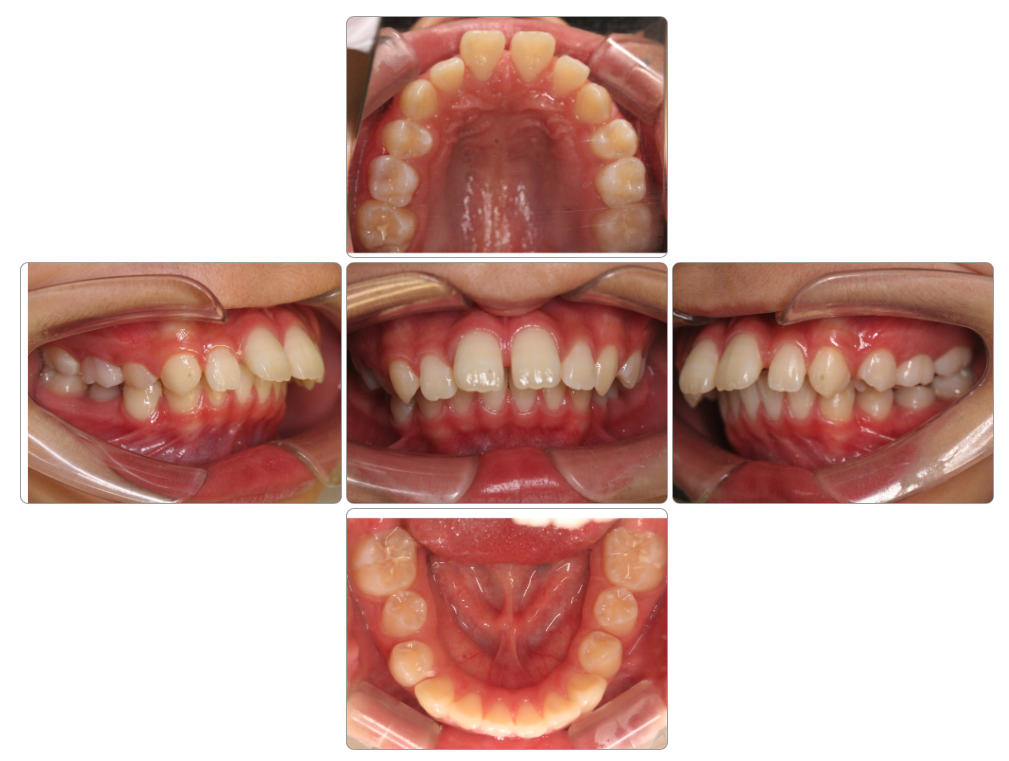

Before

after

| 初診時 | 8歳0ヵ月 |

| 治療期間 | 1年半 |

| 費用 | ¥550,000・調整料 ¥5,500/月 |

| 使用装置 | マイオブレイス・BBI・BWS |

| リスクと副作用 | |

| 原因と考察 | 顎の上がった姿勢になっており舌が前歯の裏側にまで届いていません。ここに丸飲み習慣が重なり前歯が後ろに倒されています。体幹指導と共に丸飲みにならないための食生活指導が必要です。 |